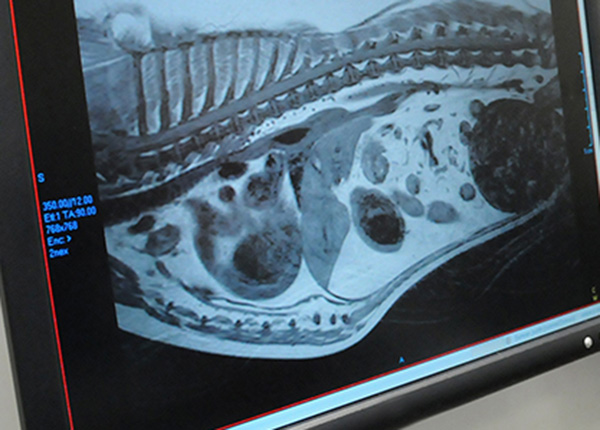

- RTG vyšetření páteře a míchy – nativní, kontrastní (myelografie…)

- zprostředkování CT vyšetření mozku a míchy